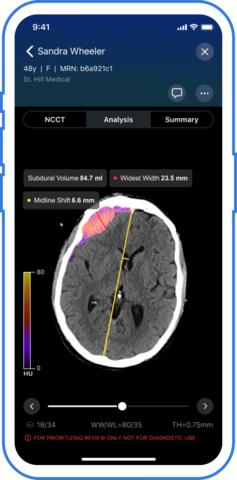

SAN FRANCISCO--(BUSINESS WIRE)--Viz.ai, the leader in AI-powered disease detection and intelligent care coordination, today announced it has received U.S. Food and Drug Administration (FDA) 510(k) clearance for Viz Subdural Plus, the first and only comprehensive solution for quantifying the size of collections like subdural hemorrhages (SDH) in the subdural space on non-contrast computed tomography (NCCT) images. The Viz Subdural Plus module is designed to support clinical-decision making by automatically labeling subdural collections and reporting measurements, including volume, thickness, and midline shift.

Chronic subdural hematoma (SDH) is projected to be the most common cranial neurosurgical condition in adults with projections suggesting approximately 60,000 new cases diagnosed annually in the United States by 20301 due to the aging population and more widespread use of anticoagulant and antiplatelet medications. Accurate quantification of subdural collections is essential for evaluating severity, monitoring progression, and informing timely treatment– especially for patients being considered for MMA embolization. Viz Subdural Plus supports clinicians in streamlining subdural collection analysis by automating what has traditionally been a manual and time-consuming measurement process. The software is available as part of the Viz.ai One platform, which is currently deployed across 1,800 hospitals and health systems.